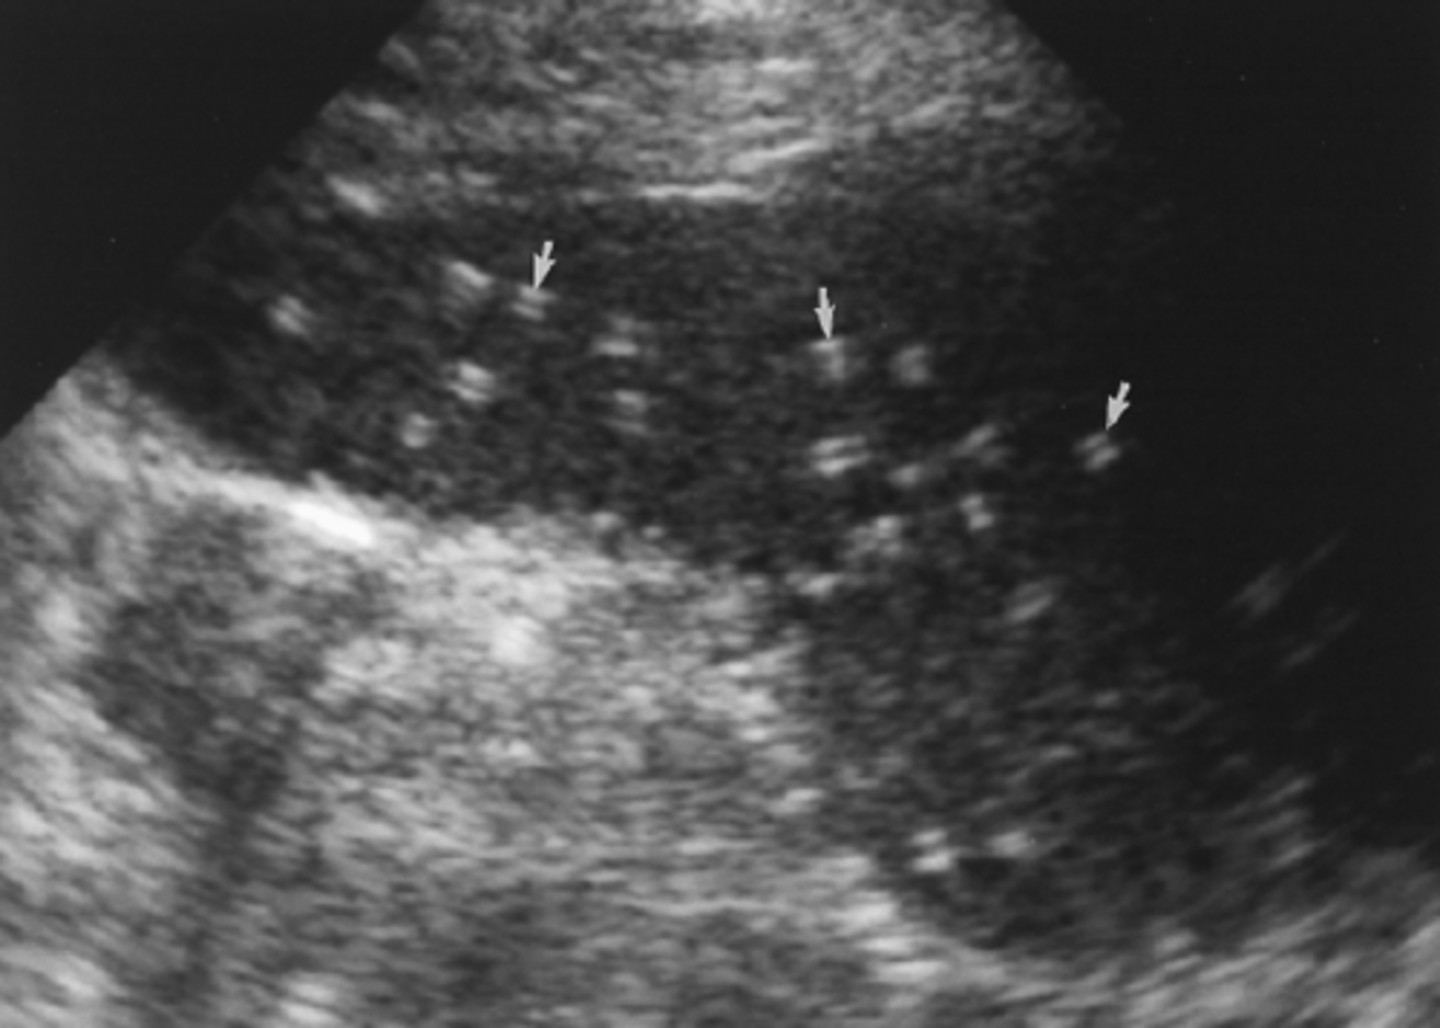

It is fairly common to see small ___ dots in the spleen. This is usually referred to as ___. They may or may not be noted on the report.

hyperechoic, granulomas